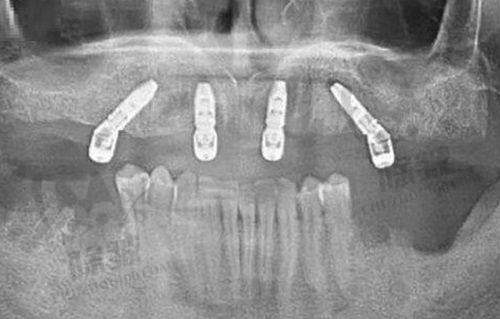

南京茀莱堡口腔引进了 3D 口腔 CT 设备、数字化的种植系统等高端设备。3D 口腔 CT 设备能够全方面、正确地评估患者的口腔条件,为制定适合的种植方案提供有力依据,大大减少了手术风险。

数字化的种植系统则让种植过程更加精细和效率高,医生可以通过该系统进行更精细的操作,提高种植的成功几率。

此外,医院还拥有数字化全景 X 光机、口腔 CT 扫描仪等设备,确保诊断正确无误,为后续的治疗提供坚实的基础。